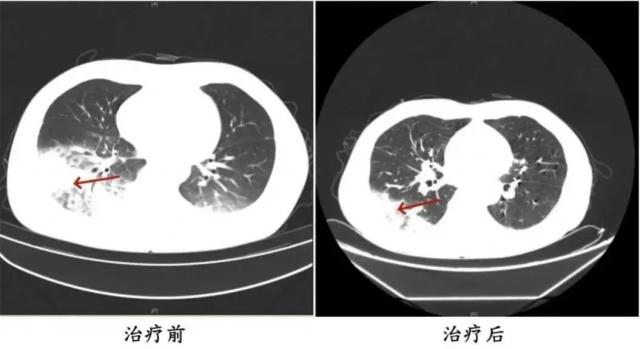

胸部 CT 展示李先生的左肺已经出现了大面积的白色影像。,肺脏几乎占了一半。肺泡灌洗 NGS 检验,最后确认“罪魁祸首”嗜肺军团菌。

治疗前和治疗后李先生肺部的对比。